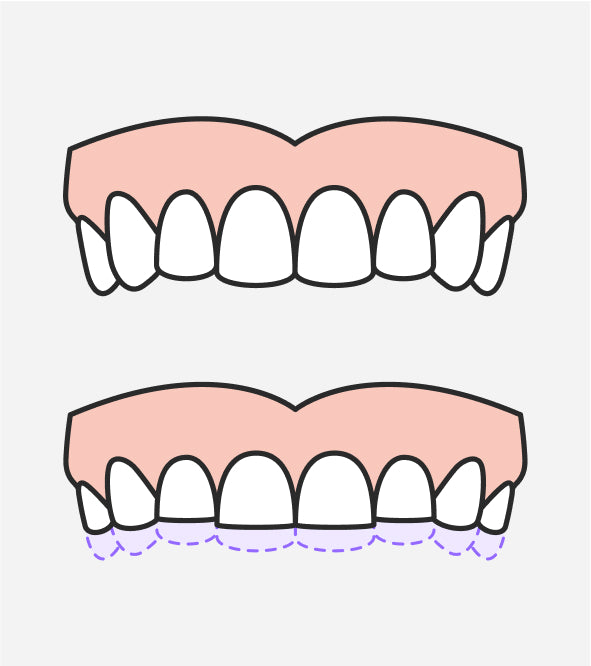

Les gouttières occlusales, également appelées gouttières de bruxisme ou gouttières de libération occlusale, sont des dispositifs amovibles conçus pour créer un espace entre les dents supérieures et inférieures. En empêchant le contact direct entre les surfaces occlusales, ces gouttières protègent les dents contre l'usure excessive causée par le grincement et le serrement répétitif. Elles peuvent être thermoformées (gouttières “prêtes à l'emploi”) ou sur mesure, fabriquées par un dentiste ou un laboratoire à partir d'empreintes de la bouche du patient.

L'avantage principal des gouttières occlusales réside dans leur capacité à protéger les dents contre l'usure excessive causée par le bruxisme. En créant un espace entre les arcades supérieure et inférieure, ces dispositifs absorbent les forces de friction et de compression générées par le grincement et le serrement des dents. Cela prévient l'amincissement de l'émail dentaire, les fissures, les éclats et l'exposition de la dentine sous-jacente.